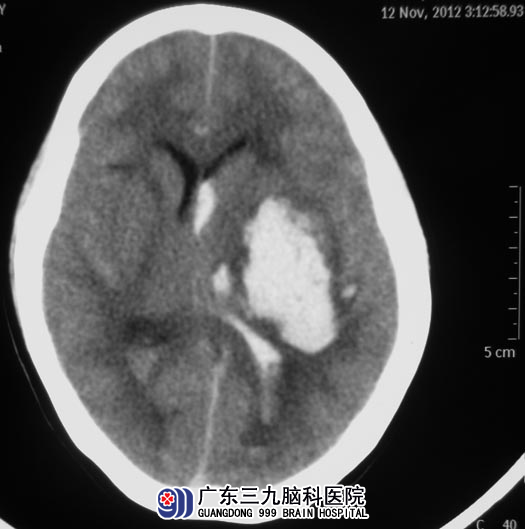

今年的秋冬交替季节,李姐突然出现意识障碍,呼之不应,伴有恶心、呕吐,急送当地医院行头颅CT检查,提示:左侧基底节区脑出血破入脑室,予保守治疗后意识无好转。http://www.999brain.com/

广东三九脑科医院头颅CTA检查提示:左侧基底节区脑出血破入脑室,未见动脉瘤或动静脉畸形。综合神经外科 鲁明主任建议立即手术治疗,全麻下行左侧基底节区脑出血钻孔引流+侧脑室穿刺外引流术;术后复查CT显示脑内血肿明显减少,血肿内给予尿激酶鞘内注射溶血凝块。

▲手术前